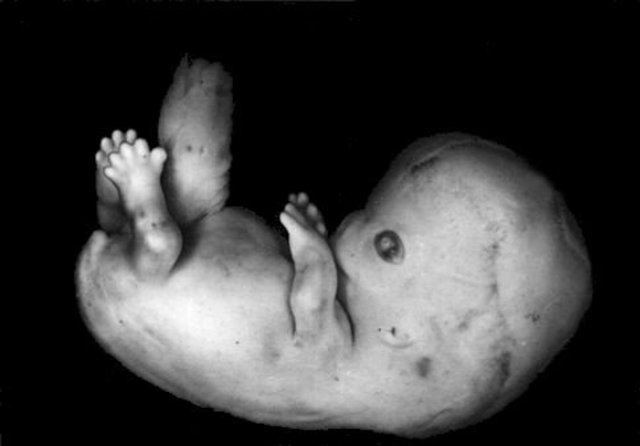

• 8 semanas. Características externas

8 semanas. Características externas

-La cabeza es casi la mitad de la longitud del feto

-La flexión cervical en de cerca de 30 grados

-Están presentes genitales externos indiferenciados

-Los ojos son convergentes

-Los párpados están fusionados

-Desaparece la cola

-Las narinas están ocluidas por unos tapones epiteliales